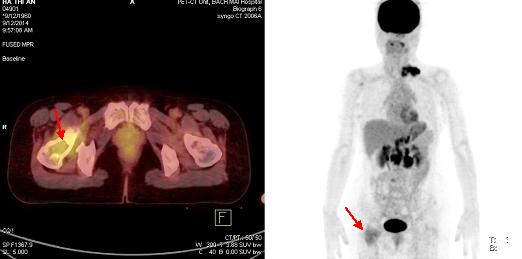

Trước điều trị: Hình ảnh tổn thương tại cổ xương đùi phải trước điều trị hóa chất (mũi tên đỏ)

Sau điều trị: Hình ảnh tổn thương tại cổ xương đùi phải sau điều trị hóa chất: Không tăng hấp thu FDG (mũi tên xanh)

Hình 10: Hình ảnh so sánh trước và sau điều trị 3 chu kì hóa chất